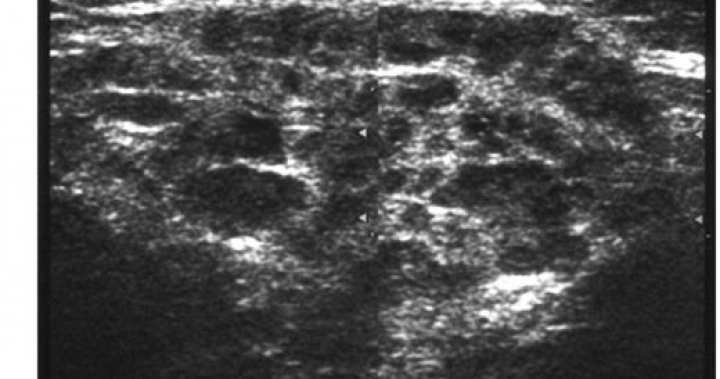

Abstract. Objectives. To evaluate ultrasonography (US) of salivary glands in primary Sjögren's syndrome (SS) and to compare US with parotid magneAbstract. Objectives. To evaluate ultrasonography (US) of salivary glands in primary Sjögren's syndrome (SS) and to compare US with parotid magneAbstract. Objectives. To evaluate ultrasonography (US) of salivary glands in primary Sjögren's syndrome (SS) and to compare US with parotid magne